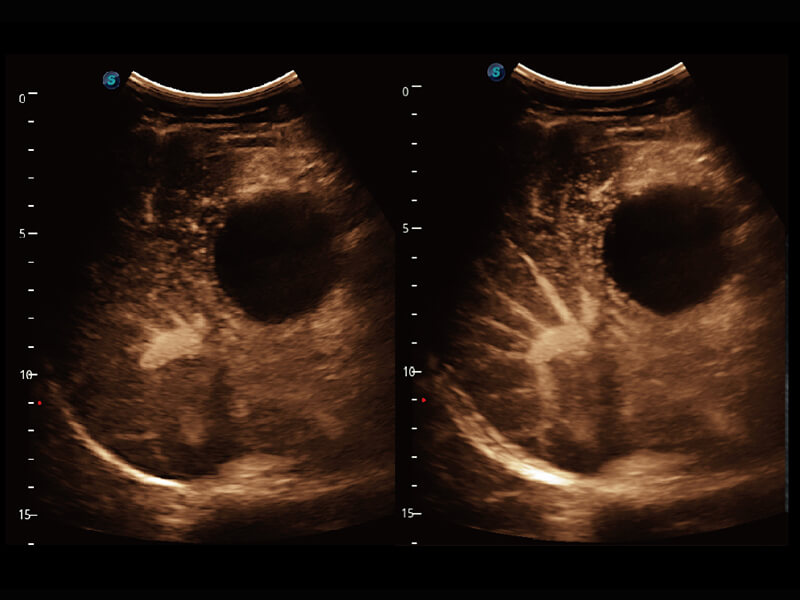

S60创新的探头工艺、高精度模数转换系统、前沿的波束重建技术,从前端信号处理每一个环节采集无损声学数据,真实还原组织原貌,再现解剖细节。

创新的超宽频带技术,为容积成像带来优质的二维图像基础,为您呈现更丰富的结构细节,栩栩如生地展示宝宝的宫内形态以及各种组织的立体结构。